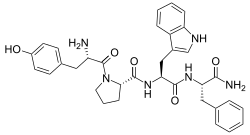

| Opioid peptides | Skeletal molecular images |

| Adrenorphin |  |

| Amidorphin |  |

| Casomorphin | |

| DADLE | |

| DAMGO |  |

| Dermorphin | |

| Endomorphin |  |

| Morphiceptin |  |

| Nociceptin |  |

| Octreotide |  |

| Opiorphin |  |

| TRIMU 5 |  |